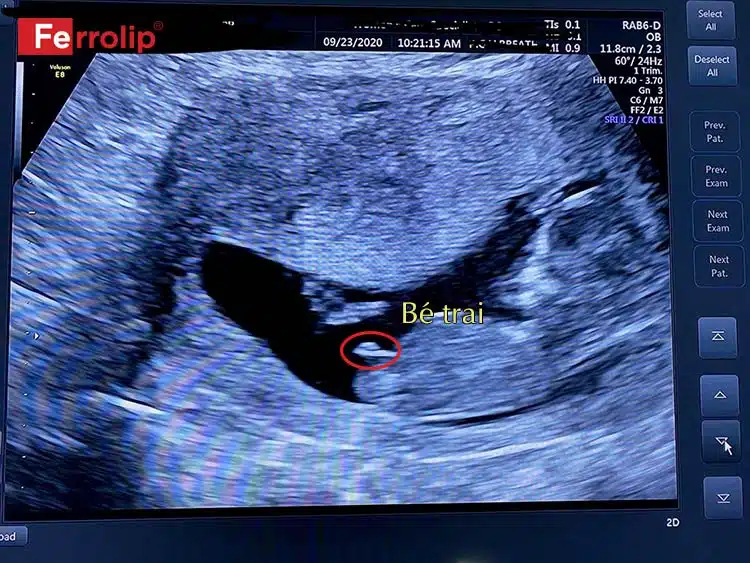

Khi mang thai, nhiều mẹ bầu thường tò mò về giới tính của thai nhi và thử nghiệm một số cách truyền thống để dự đoán. Một trong những phương pháp đơn giản là quan sát hình dáng túi thai. Theo dân gian, nếu túi thai có hình tròn hoặc bầu dục, nhiều khả năng bạn sẽ sinh con gái. Ngược lại, túi thai hình dài thường báo hiệu một bé trai.

Khi mang thai, việc xác định giới tính thai nhi luôn là một chủ đề thú vị. Một trong những cách truyền thống mà nhiều người thường sử dụng là nhìn vào hình dạng của túi thai. Thường thì, túi thai hình dáng dài được cho là dấu hiệu cho thấy thai nhi có khả năng là con trai, trong khi túi thai hình tròn hoặc bầu dục thường chỉ ra rằng có thể là con gái.

Khi mang thai, nhiều bậc phụ huynh thường tò mò về giới tính của em bé trong bụng. Một trong những cách dân gian được truyền miệng là quan sát hình dạng túi thai. Theo đó, túi thai hình dáng dài thường được nhận định là dấu hiệu của bé trai, trong khi túi thai có hình tròn hoặc bầu dục thường là bé gái.

Hình ảnh túi thai là một phần quan trọng trong hành trình mang thai của người mẹ. Theo như kinh nghiệm dân gian, hình dáng của túi thai có thể dự đoán giới tính của thai nhi. Túi thai hình dài thường được cho là dấu hiệu cho biết mẹ đang mang bầu bé trai, trong khi túi thai hình tròn hoặc bầu dục thường được xem là dấu hiệu của bé gái.